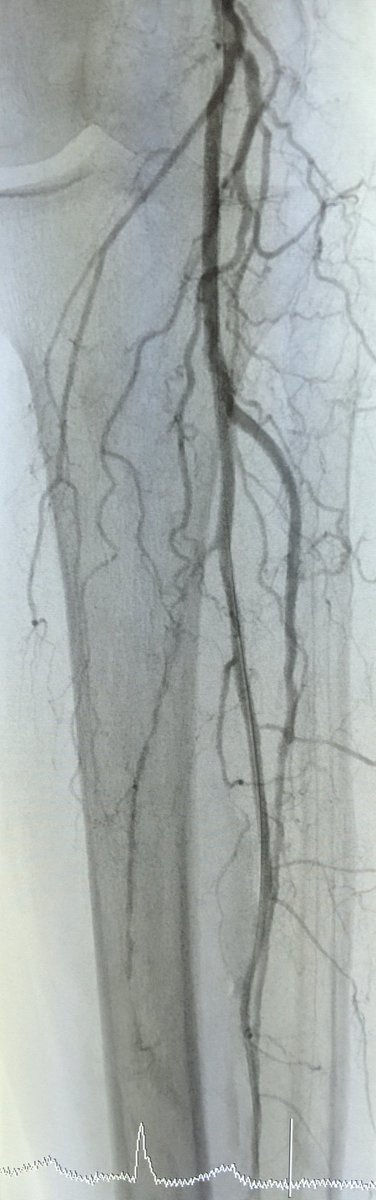

@ColoradoIR #CLIFighters Non-healing wound d/t inflow disease. Re-entry leads to ABI improvement from 0.4 to 1 and 2+ DP. @CLI_Global @kmadass @SDhandMD @KMSchramm @UCD_IR #stopthechop #mylegmylife

pj_rochon's tweet image. @ColoradoIR #CLIFighters Non-healing wound d/t inflow disease. Re-entry leads to ABI improvement from 0.4 to 1 and 2+ DP. @CLI_Global @kmadass @SDhandMD @KMSchramm @UCD_IR #stopthechop #mylegmylife